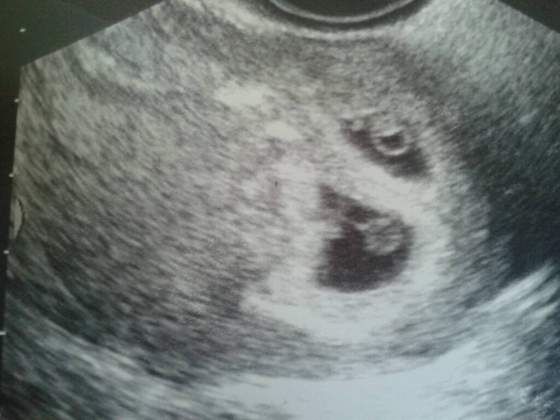

Ciąża bliźniacza

Selenaris po tych 8 dniach pecherzyki dalej nie byly rowne ale w srodku dzidzie byly podobnej wielkosci. Sprobuje zalaczyc zdjecie ktore wyszlo mi wtedy na skanie. Przy okazji przepraszam Nathani ze Cie w blad wprowadzilam bo to jest fotka z 7 tygodnia i chyba juz tutaj glowki widac. Smieszne to takie bo wygladaja jak ludki z kasztanow ;-)

Z tego co pamiętam wcześniej między pęcherzykami też była duża różnica, tak jak pisałam wcześniej jeden dwa razy mniejszy od drugiego. To zdjecie, które wkleiłam to juz po tych 8 dniach zrobione było